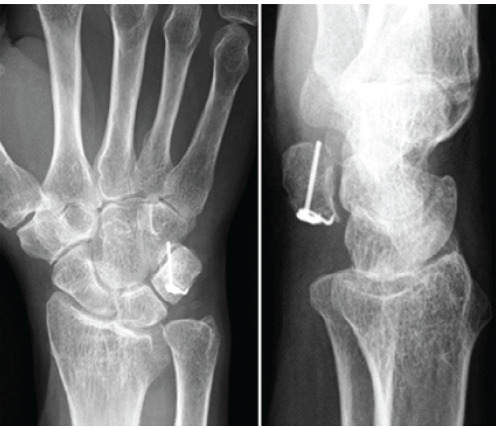

The post-operative course was uneventful. Active range-of-motion (ROM) exercises were initiated after the splint was removed. At 3 months, plain radiographs confirmed bone union, and the patient had resumed daily and social activities without restriction. At 12 months (Figs. 4 and 5), she reported no wrist pain and had returned to normal activities without limitations.

Figure 4: Radiographs at the 12-month follow-up demonstrate bone union with proper anatomical alignment and no pisotriquetral degenerative changes.

Radiographs demonstrated complete union and proper alignment. The implant remained well-positioned, with no sign of loosening or migration, and no degenerative changes were observed in the pisotriquetral joint.